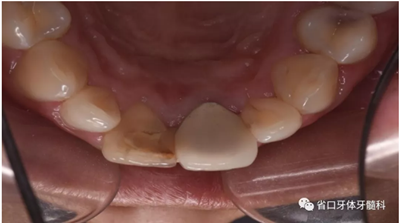

口腔檢查:口腔衛(wèi)生狀況一般,11牙冠變色,近中鄰面見齒色填充物,舌側(cè)窩內(nèi)見白色充填物,邊緣見黑色齲壞物,近中探及懸突,叩痛(土),松(—),冷診無反應(yīng);21烤瓷全冠修復(fù),烤瓷冠顏色未知,唇側(cè)齦緣發(fā)黑,叩痛(土),松(—)。圖1/2

圖1 治療前患牙唇側(cè)觀